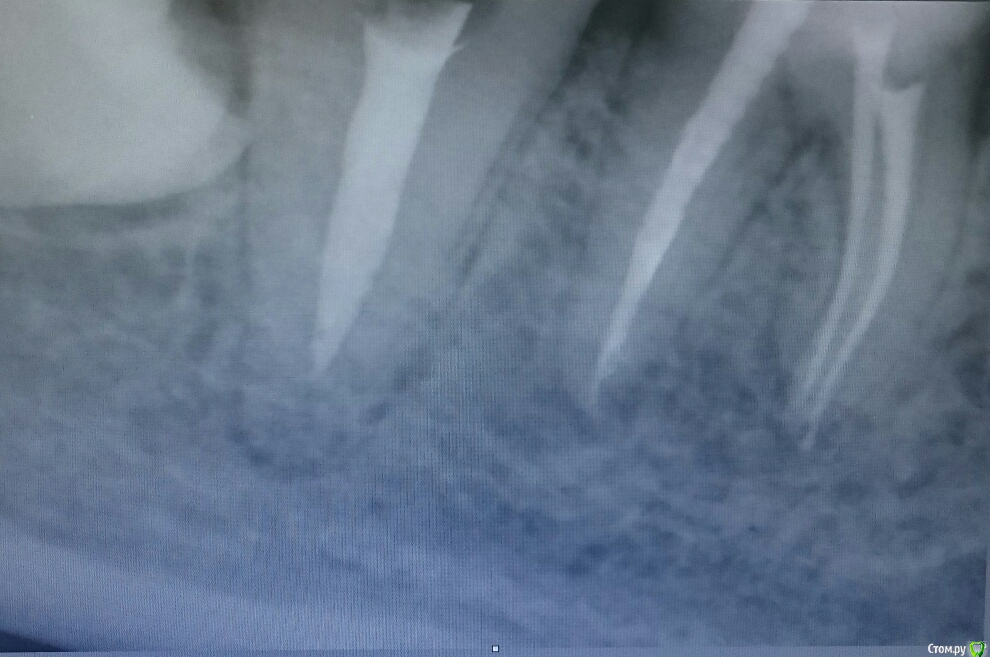

55dantist Опубликовано 21 ноября, 2015 Поделиться Опубликовано 21 ноября, 2015 Пациентка обратилась с острым периодонтитом. Обработка канала протейперами, гипохлор, вода,хлоргексидин. Апекслокатор показал верхушку. Запаковались латеральной конденсацией. А на снимке такая картина ((( Вопрос: Апекслокатор врет? Или на самом деле клиническая верхушка здесь? Кто-нибудь видит продолжение канала?П.с.: КЛКТ не предлагать( нет его по близости)П.п.с:пациентку отпустили с таким пломбированием, через три дня ничего не беспокоит. Ссылка на комментарий

DR.P Опубликовано 21 ноября, 2015 Поделиться Опубликовано 21 ноября, 2015 Скорее всего в этом месте было латеральное ответвление, вот апекс и пищал. Какой силлер? И почему вода? Ссылка на комментарий

DmitrySH Опубликовано 21 ноября, 2015 Поделиться Опубликовано 21 ноября, 2015 Если нет уверенности в аплоке, то лучше лишний раз с файлами на снимок сходить. Тоже думаю что пищал на широкую латераль. 1 Ссылка на комментарий

dima3M Опубликовано 1 декабря, 2015 Поделиться Опубликовано 1 декабря, 2015 Одновременно работая с Rypex и Моритой заметил, что в таких случаях Райпекс врет чаще (при широких каналах).Рентген и бумажный штифт с "кровяной пробой" помогают точнее локализовать апекс.( и в случве конфликта, тьфу тьфу тьфу...не снимок ли будет критерием оценки результата?) Ссылка на комментарий